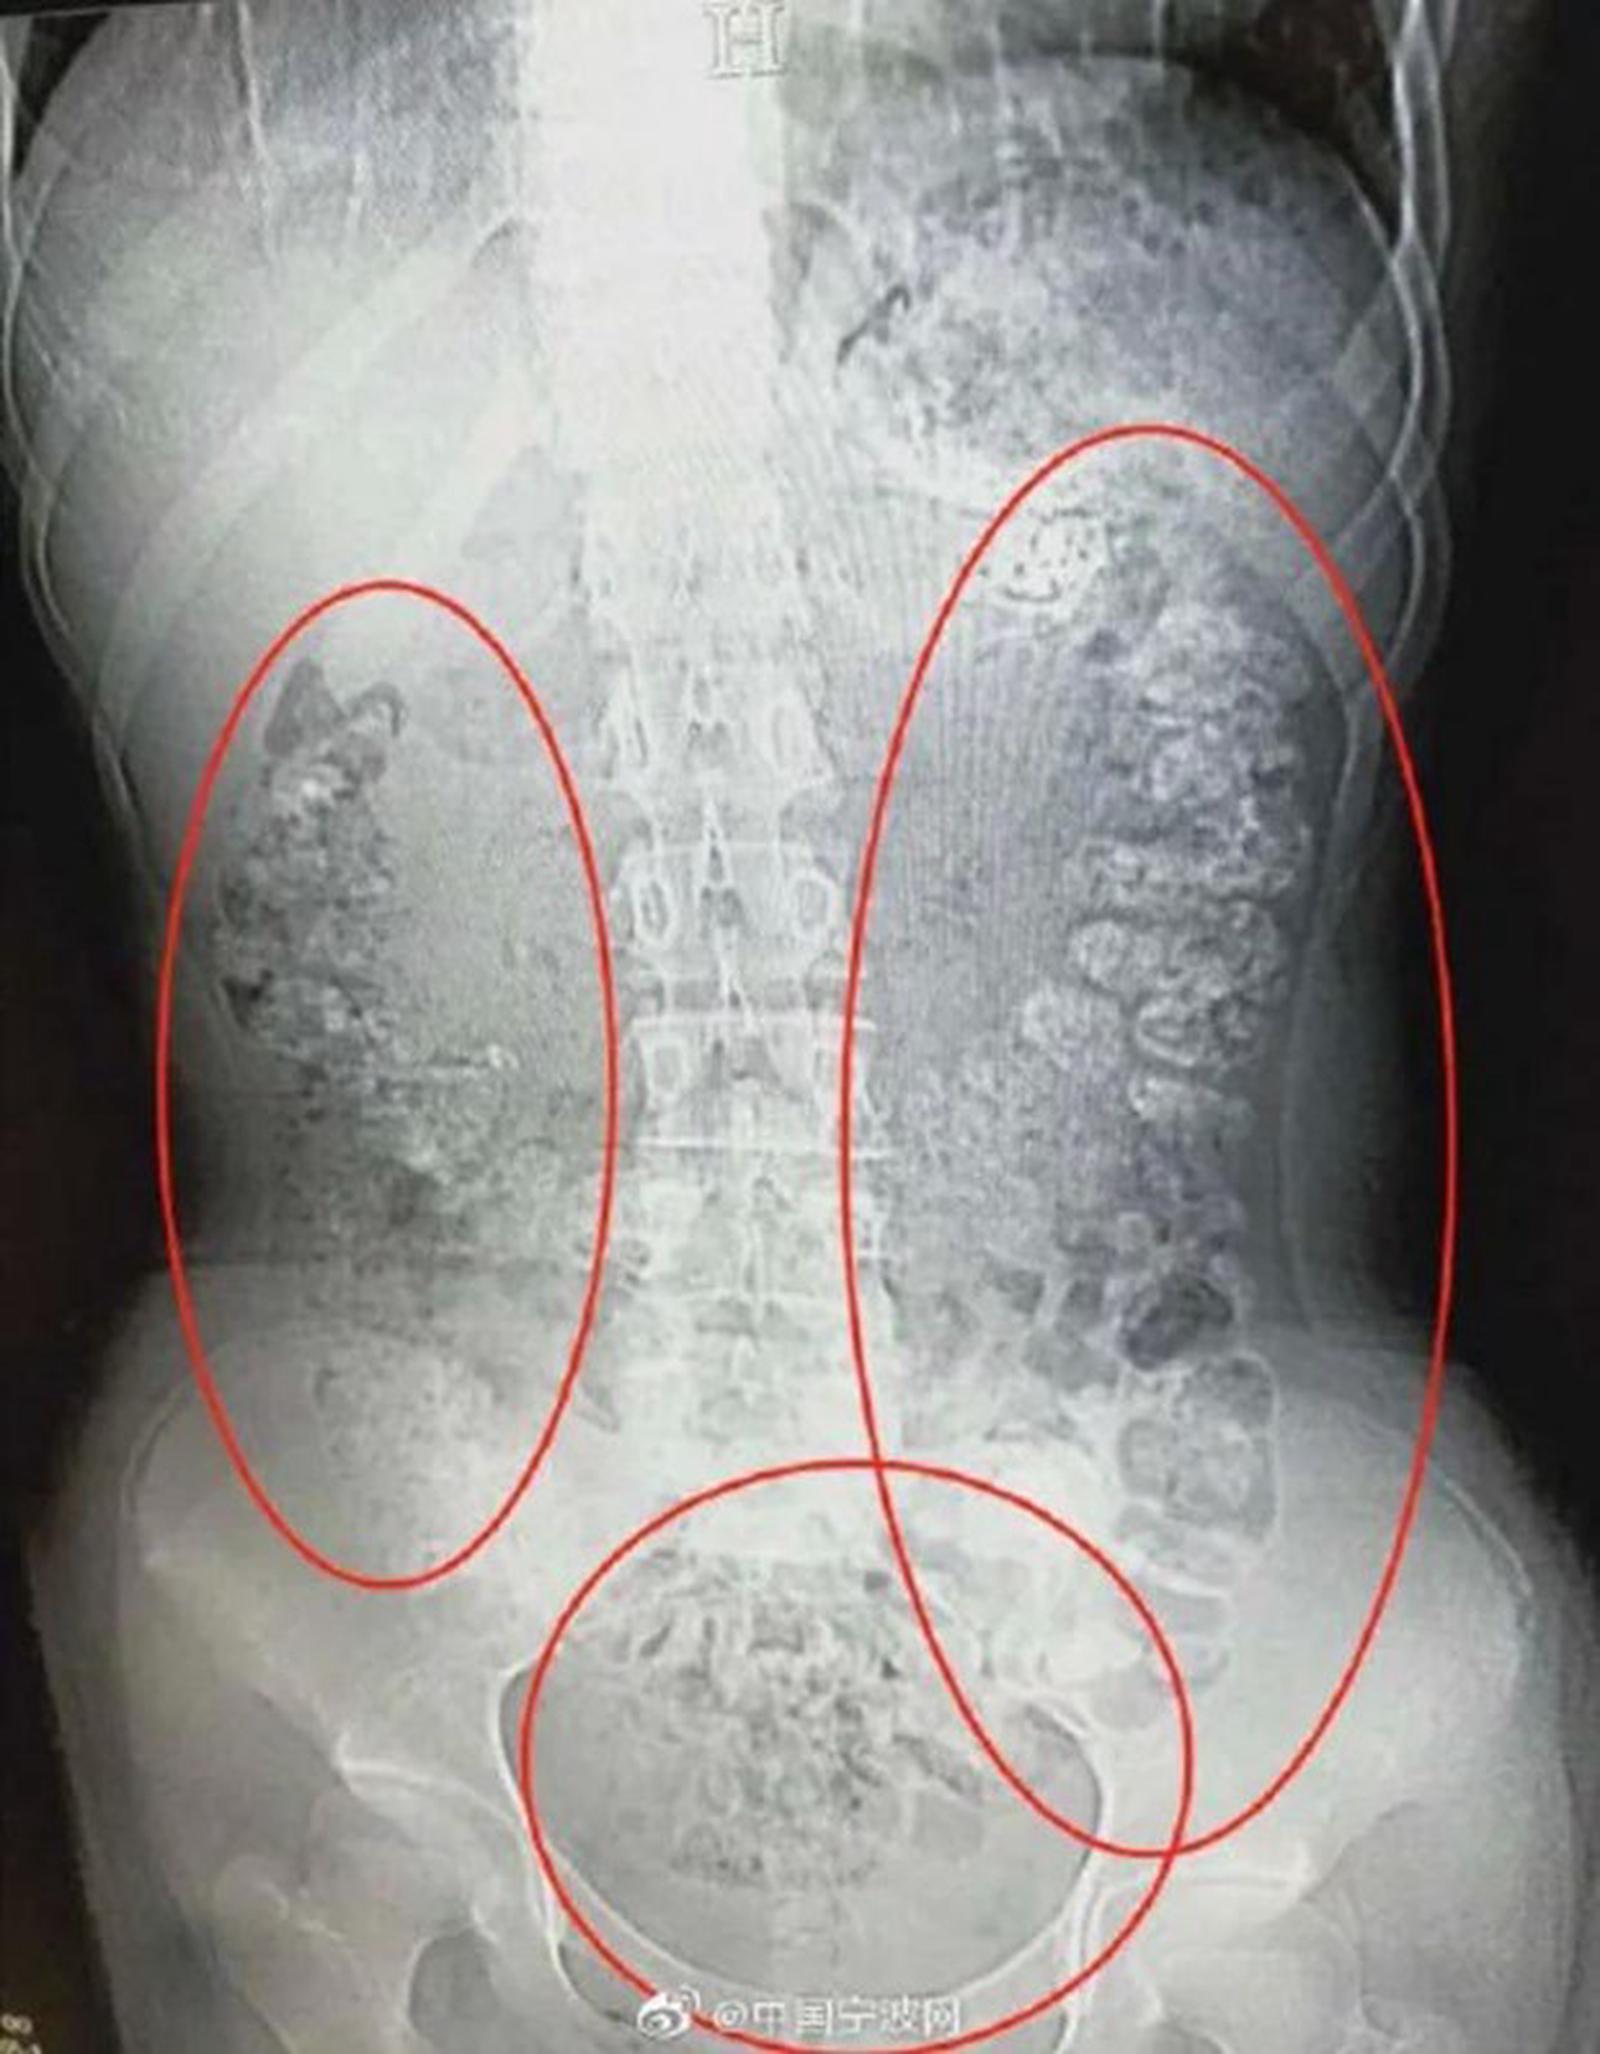

Phát hiện bụng cô bé phình to bất thường, các bác sỹ đã quyết định đưa bệnh nhân này đi chụp cắt lớp. Kết quả chụp cắt lớp cho thấy hàng trăm vật thể nhỏ hình tròn nằm trong khắp các cơ quan nội tạng, từ dạ dày, đại tràng, ruột và hậu môn.

Sau khi cùng nhau thảo luận, các bác sỹ kết luận những vật thể nhỏ này là các hạt trân châu chưa được tiêu hóa hết. Bác sỹ Zhang Louwei đã hỏi cô bé xem bệnh nhân có ăn gì khó tiêu trong vài ngày qua hay không. Cô bé thừa nhận đã uống một cốc trà sữa từ 5 ngày trước khi nhập viện.

Tuy nhiên, bác sĩ Zhang cho rằng số hạt trân châu này được tích tụ do cô bé đã uống trà sữa trân châu trong một thời gian dài.

Các hạt trân châu vẫn mắc kẹt trong hệ tiêu hóa. (Ảnh: 9GAG)